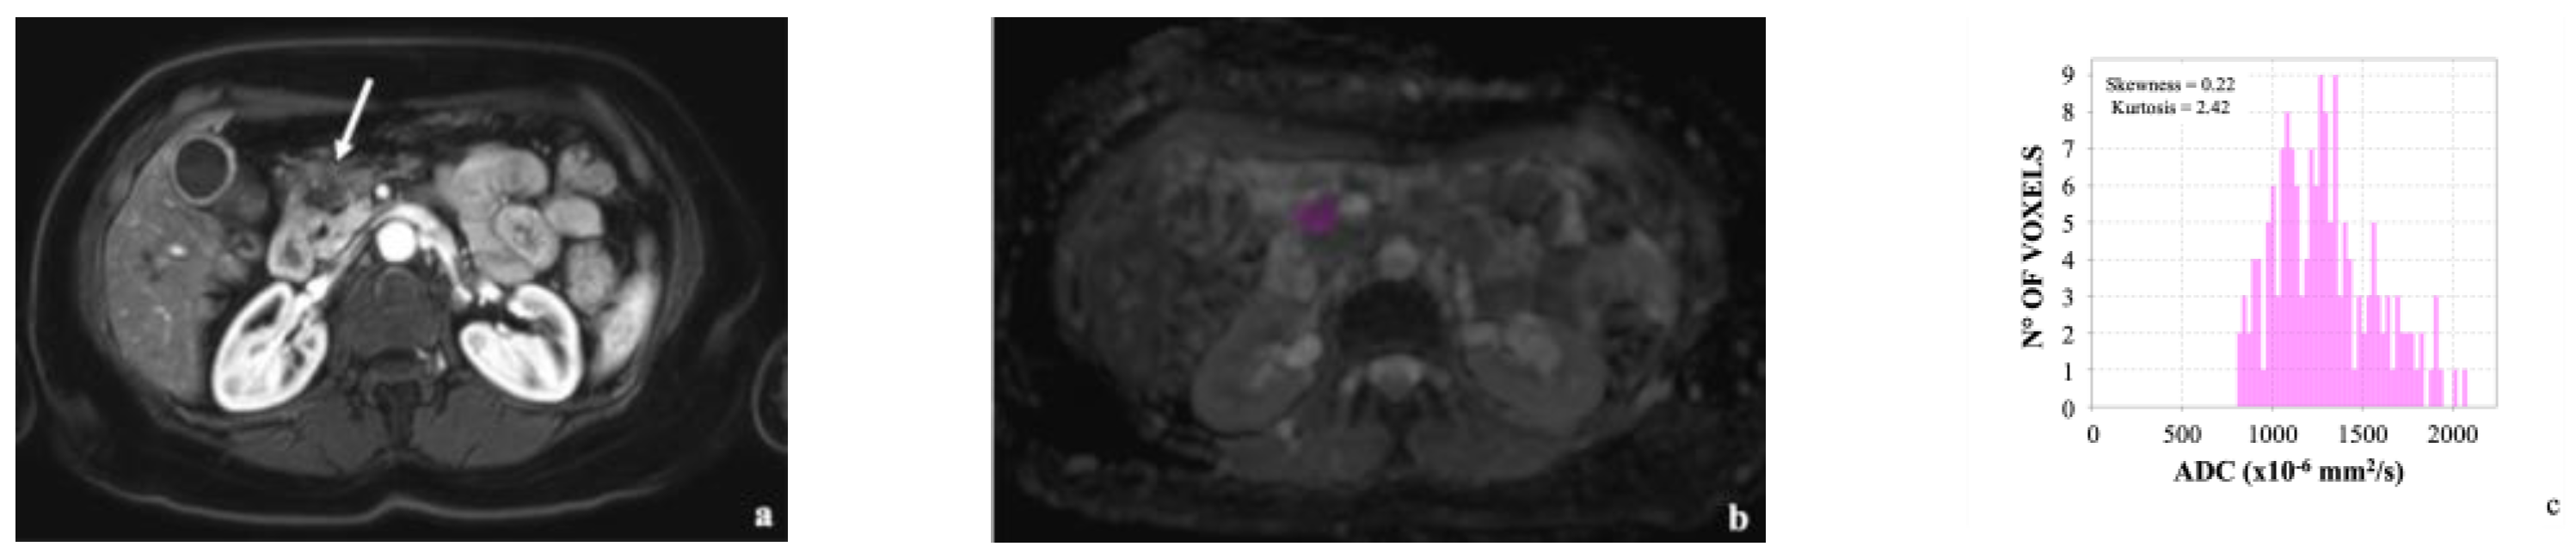

| Skewness | 0.6 (−0.6;3.3) | 0.2 (−1.2;1.8) | 0.005 |

| Kurtosis | 4.3 (1.7; 17.3) | 3.8 (2.1; 11.1) | 0.032 |

| Optimal Cut-off | 0.23 | 3.90 |

| Sensitivity | 98.6 (92.5–100) | 47.6 (36.4–58.9) |

| Specificity | 41.7 (27.6–56.8) | 100 (91–100) |

| PPV | 71.7 (66.6–76.3) | 100 (-) |

| NPV | 95.2 (73.5–99.3) | 46.9 (41.8–52.1) |

| Accuracy | 75.8 (67.2–83.2) | 64.2 (54.9–72.7) |